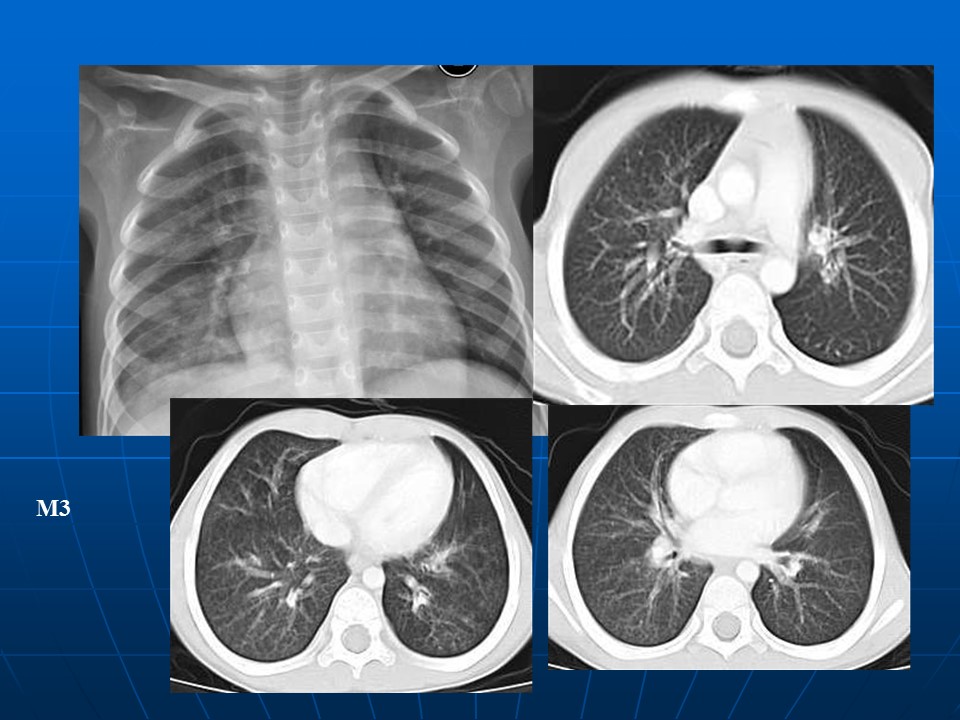

HRCT树芽征的诊断价值